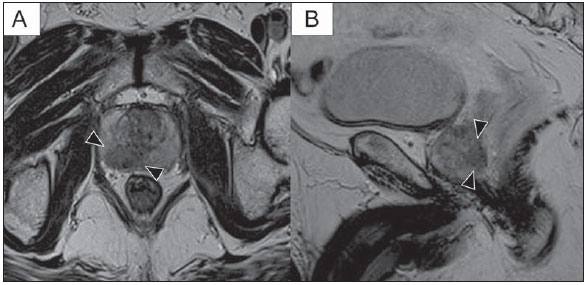

Acima, podemos observar um aspecto típico de tumor na zona periférica, em imagens pesadas em T2, mostrando uma lesão nodular hipointensa no T2 à direita, marcada com cabeças de seta nos planos axial (A) e sagital (B).